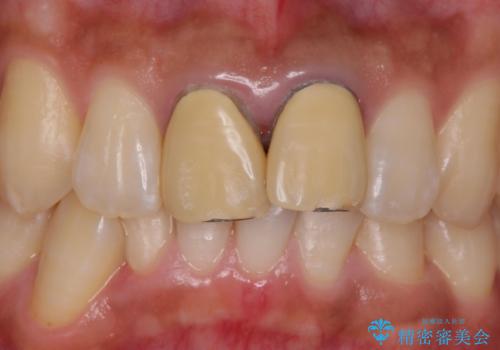

- 仮歯:11,000円×2本 / e-maxクラウン:77,000円 合計176,000円費用は治療当時の料金となります

歯のガタつきも解消することができました。

e-maxクラウンでは仮着ができませんが、今回は一回でご満足いただける修復ができました。